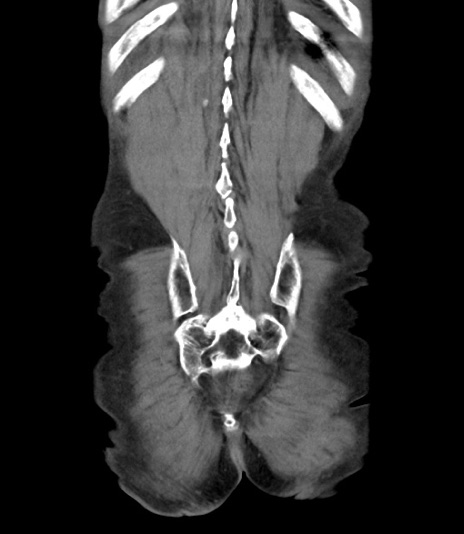

横断像

【症例】 70歳代男性

【主訴】右鼠径部腫瘤、疼痛

【現病歴】本日朝より上記主訴あり、受診。

【既往歴】膀胱癌にて膀胱全摘、両側尿管皮膚瘻

【データ】WBC 5600、CRP 0.56